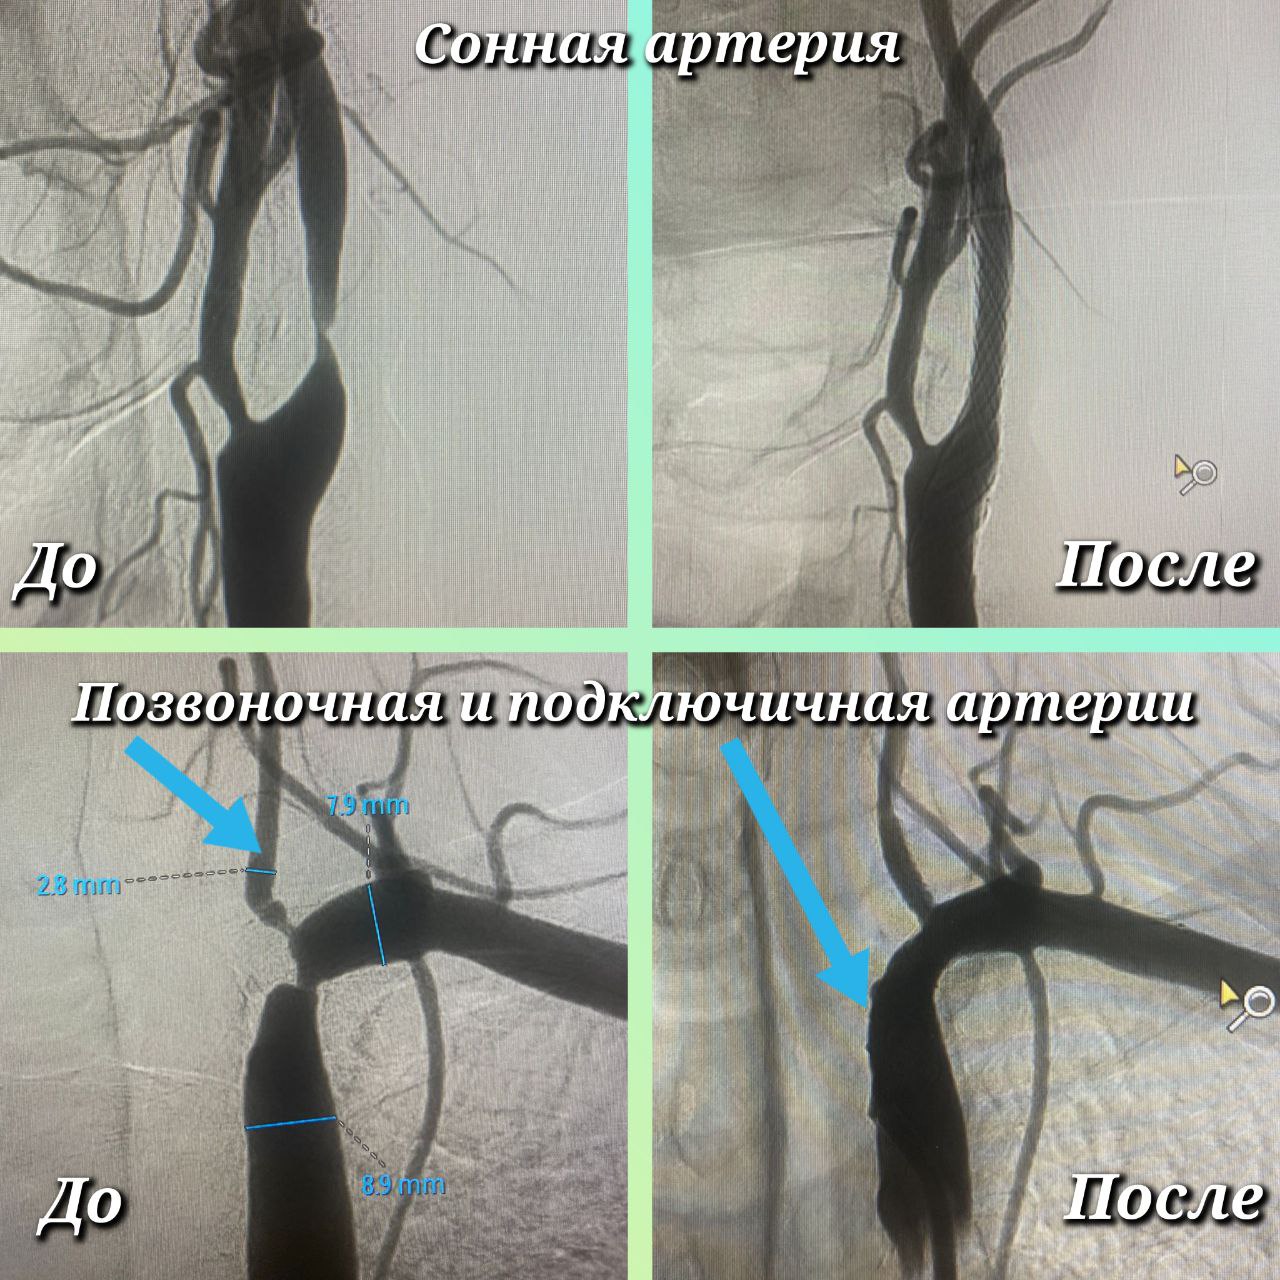

Чтобы в первую очередь избежать инсульта, оперативное лечение Максим Бессмертных начал с сонной артерии. Сначала восстановил её проходимость специальным баллонным катетером, а затем для предотвращения повторной окклюзии установил стент. Те же самые манипуляции выполнены на подключичной и позвоночной артерии. Всё это – за одну операцию. Малоинвазивное рентгенэндоваскулярное вмешательство длилось около двух часов.